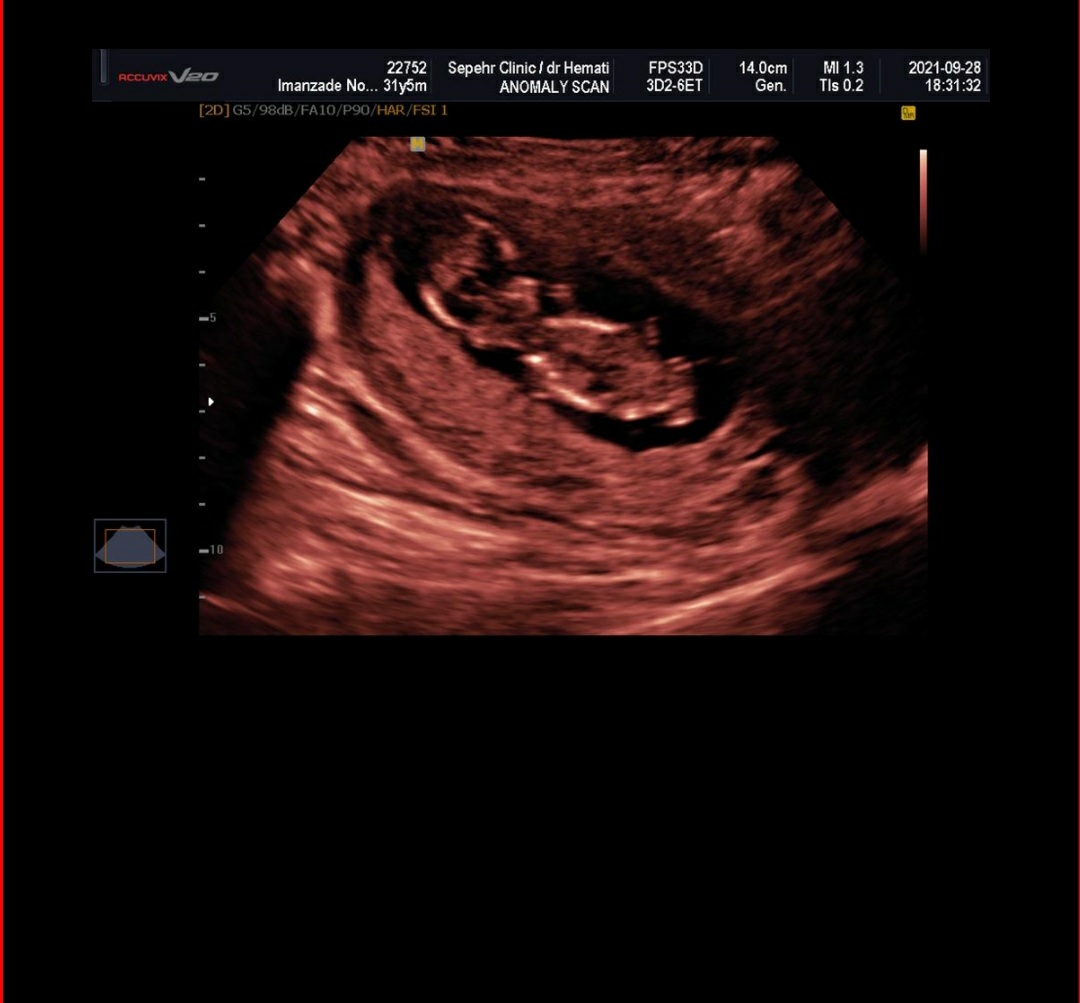

سلام به روی گلتون مامان جان

خیلی خیلی مبارکتان باشد ریسک محاسبه شده برای سندروم های ژنتیکی تریزومی ۲۱ و تریزومی ۱۸ و 13 همگی در محدوده کم خطر قرار داشته و منفی هستند. در حال حاضر نیاز به هیچ بررسی دیگری نیست جان دلم و صرفاً در هفته هجده بارداری مانند تمامی مادرانی که در محدوده کم خطر قرار دارند، سونوگرافی آنومالی اسکن برای ارزیابی ساختارهای بدن جنین و همچنین آزمایش Ntd screen برای ارزیابی اختلالات لوله عصبی (این بررسی ضرورت جدی انجام ندارد و در صورت صلاحدید پزشکتان درخواست گردد) را انجام دهید،، سونوگرافی هم خوب است❤️